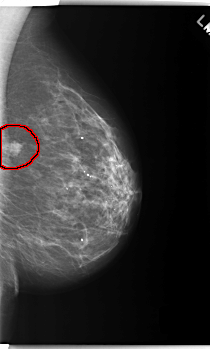

C_0218_1.LEFT_MLO

LEFT_MLO LINES 5928 PIXELS_PER_LINE 3560 BITS_PER_PIXEL 12 RESOLUTION 50 OVERLAY

FILE: C_0218_1.LEFT_MLO.OVERLAY

TOTAL_ABNORMALITIES 1

ABNORMALITY 1

LESION_TYPE MASS SHAPE LOBULATED MARGINS MICROLOBULATED

ASSESSMENT 5

SUBTLETY 5

PATHOLOGY MALIGNANT

TOTAL_OUTLINES 1

BOUNDARY